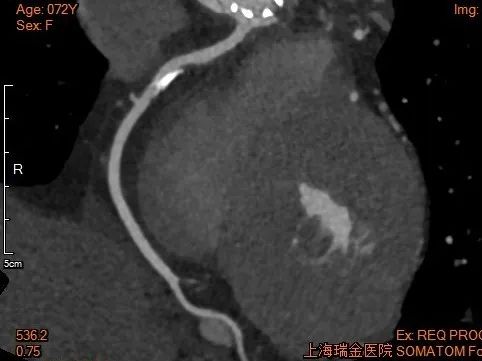

术后1w——冠脉CTA

● 术前应进行充分CT评估,摒弃唯冠脉高度论,需要结合窦部大小及高度、STJ大小、瓣叶的长度、瓣叶增厚和钙化分布情况等因素,综合考量冠脉风险。